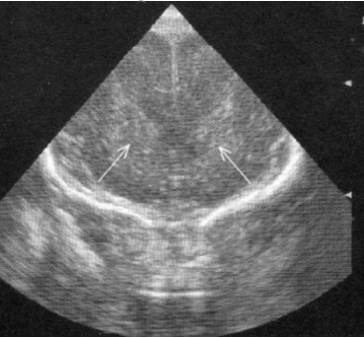

Neonatology Grade 0 PVL 1 Image